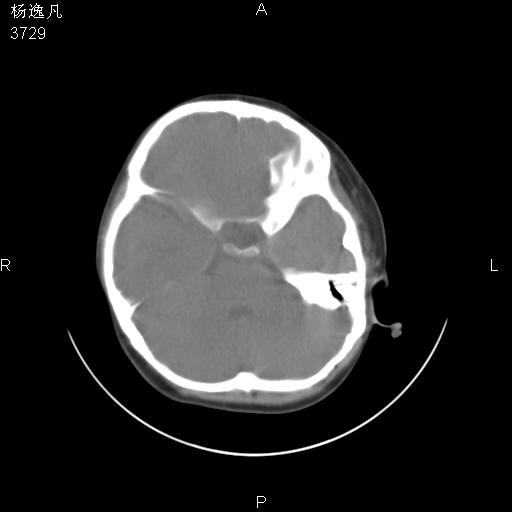

男性,5岁,面部受外伤,余无特殊

软组织窗

1、右面部及颞部软组织肿胀。

2、腺样体肥大。

头颅ct平扫未见明确外伤性征象,右侧面部及颞部软组织肿胀,后鼻腔软组织影增大,增厚,鼻咽顶部变窄,考虑鼻咽腺样体增值肥厚。